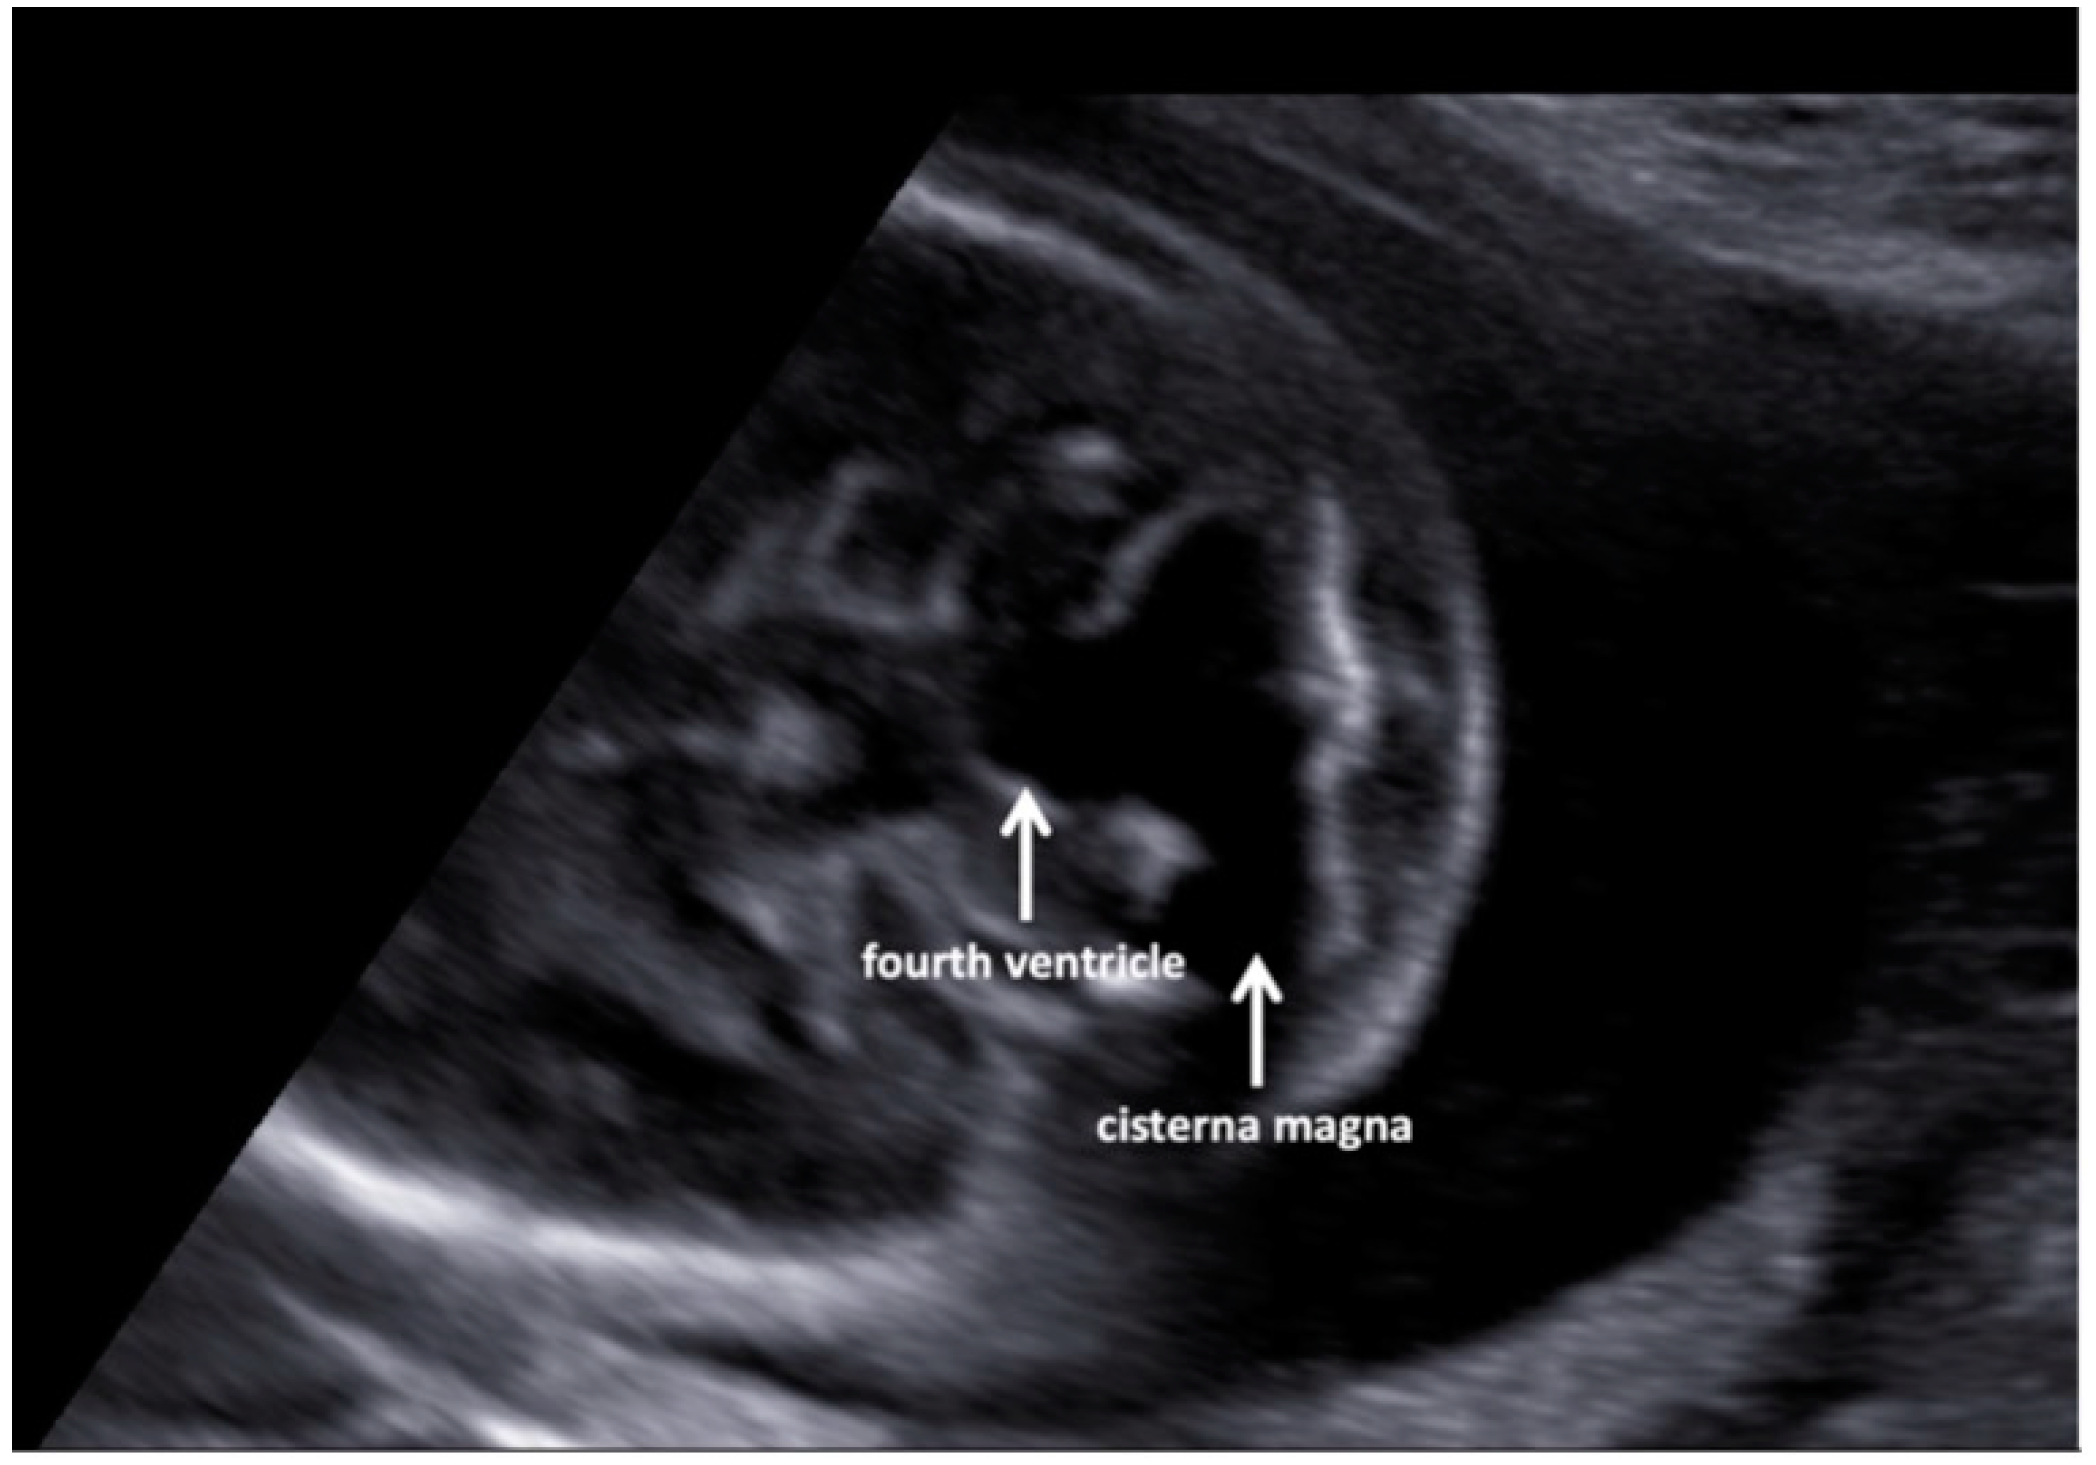

A fetal ultrasound (USA) in a 35-year-old Italian woman revealed multiple malformations despite first-trimester screening showing regular parameters (nuchal translucency, NT, 1.9 mm; crown-rump length, CRL, 7 mm). Additionally, the cell-free DNA screening test for fetal aneuploidy had a Z score in the normal range. The pregnancy was uneventful until the second level US examination at the 19th gestation week when the left-sided diaphragmatic hernia (CDH), dextroposition of the heart, and severe aortic coarctation associated with a ventricular septal defect, and a Dandy–Walker malformation (Figure 1 and Figure 2) were highlighted.

Figure 2. Axial views of the fetal head at the level of the mid-fourth ventricle (20 weeks of pregnancy), showing continuity of the fourth ventricle and cisterna magna.